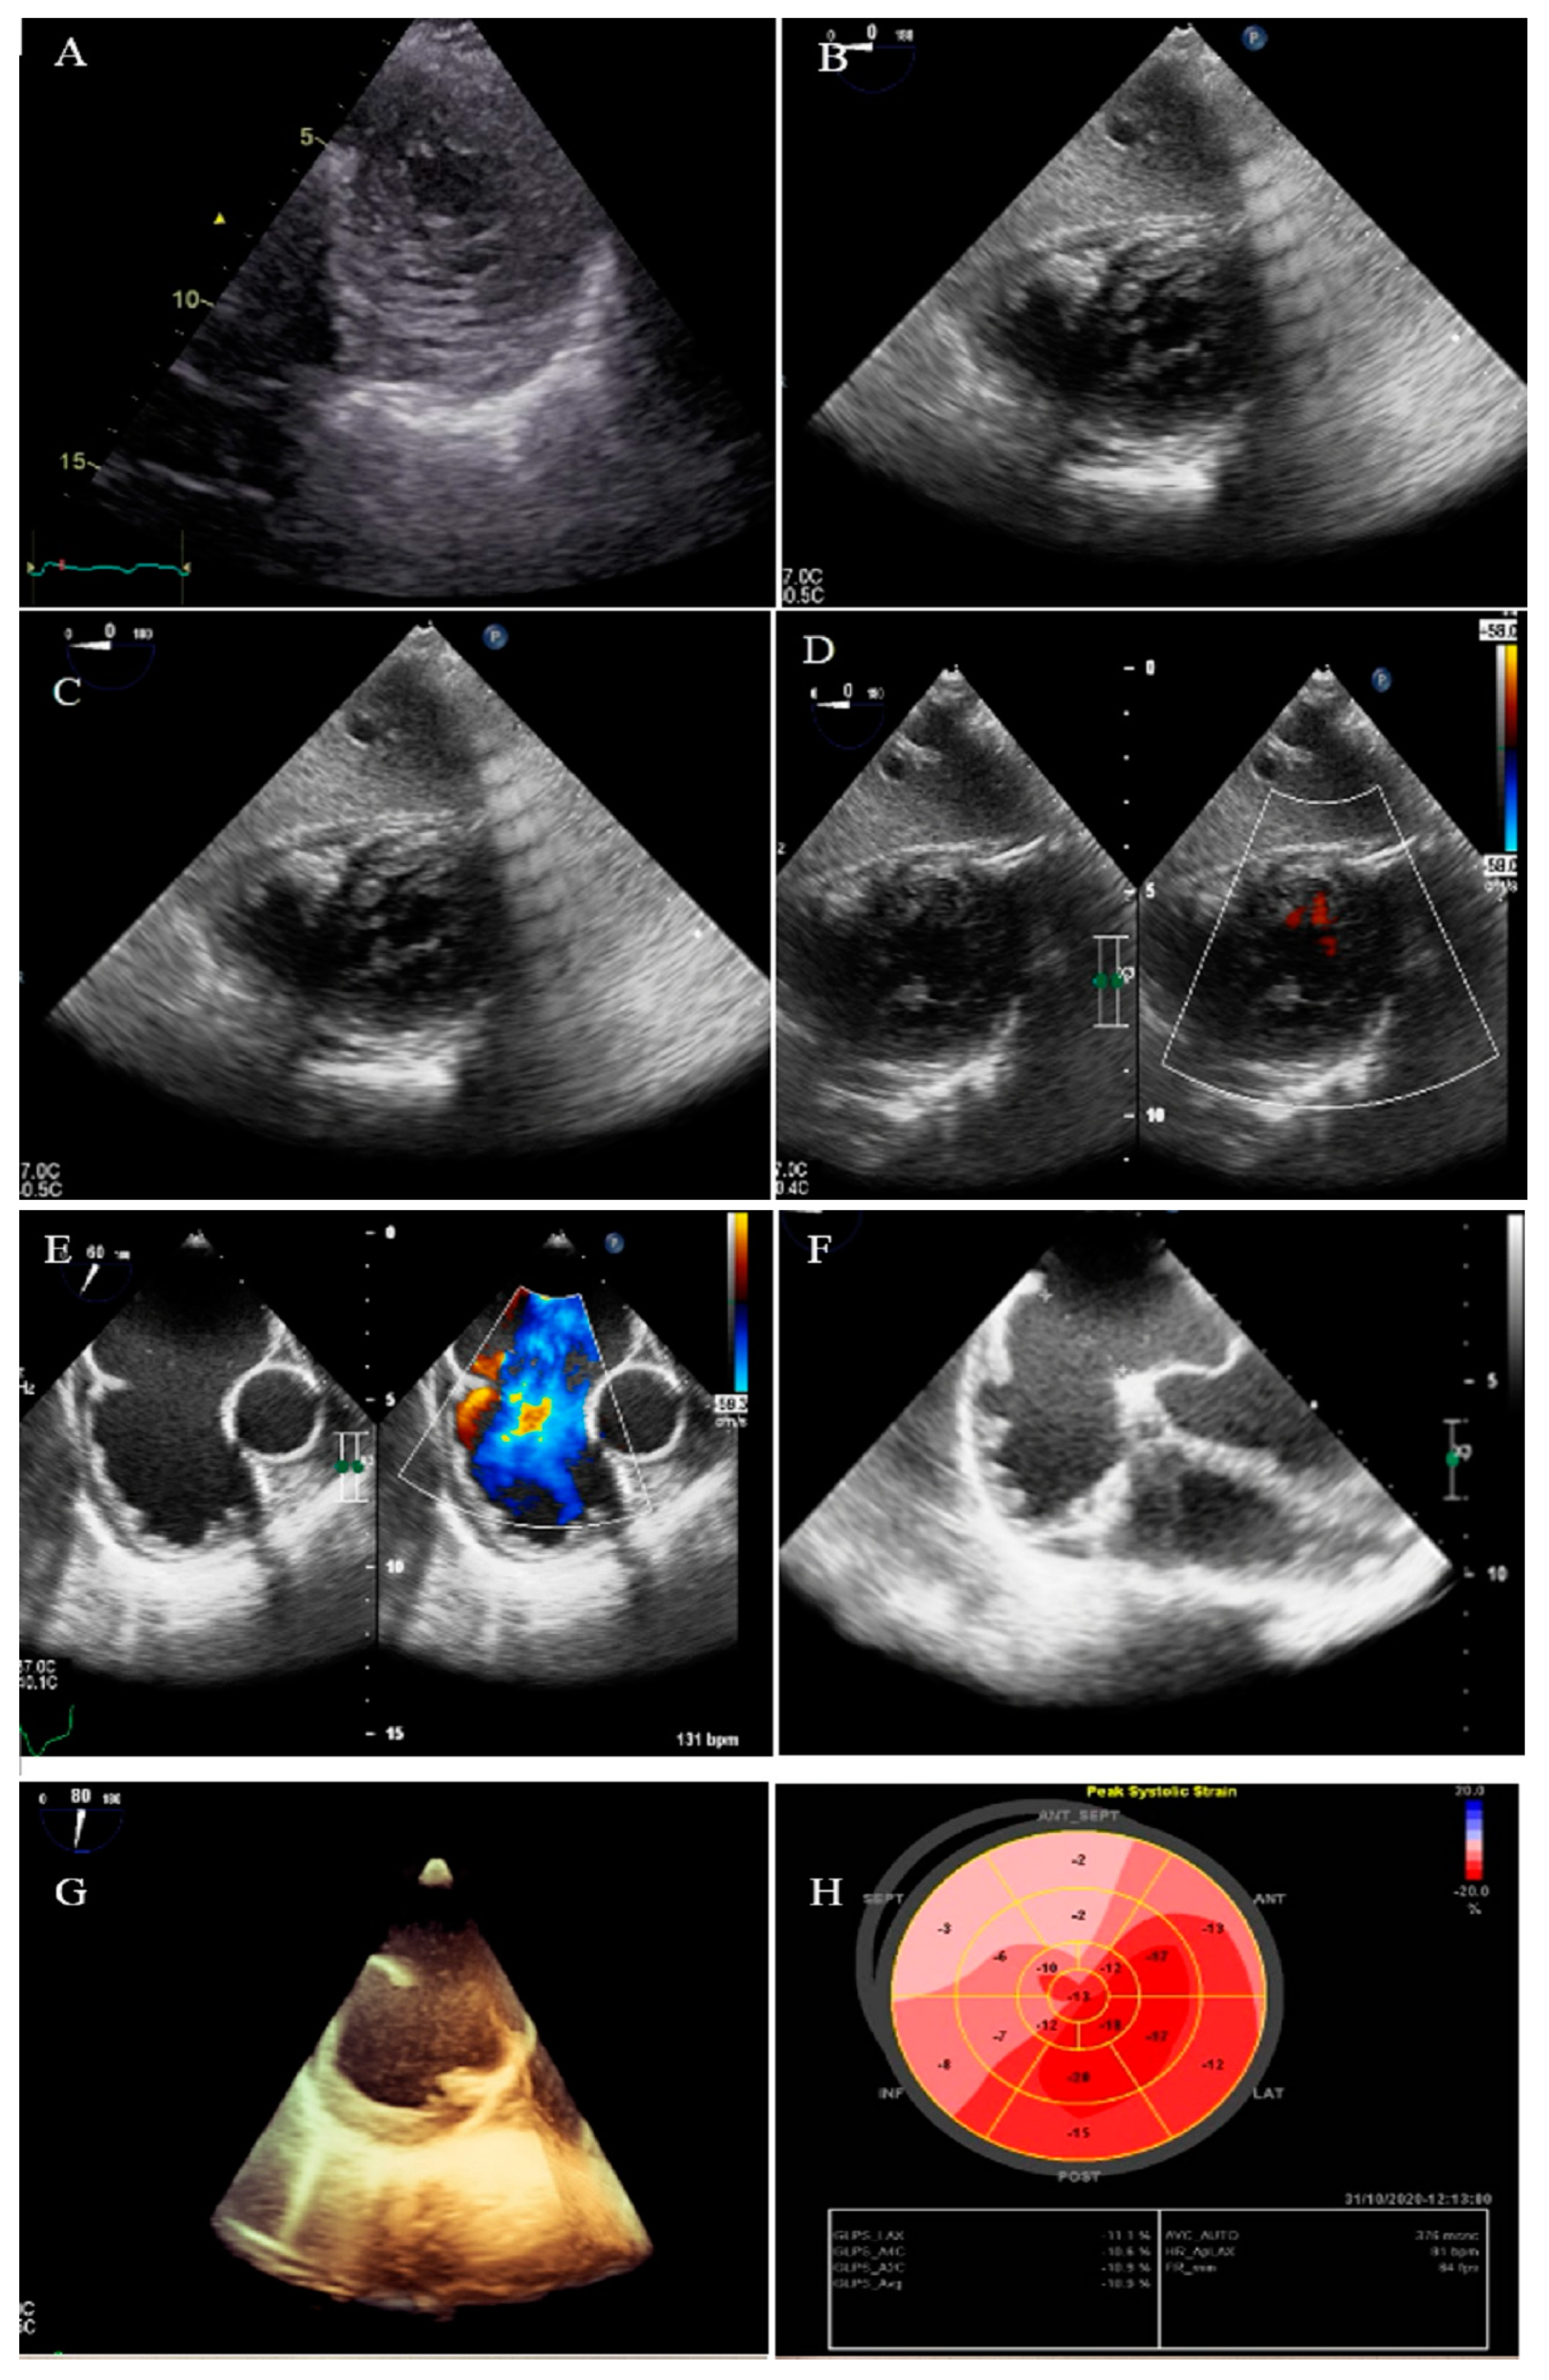

2.1. Case #1. NCLV and Coarctation of the Aorta

| 1 | M | 47 | Easy fatigability and mild hypertension since two years ago | HTN | NCLV, reduced LVEF (45%) | Coarctation of aorta | + | + | Carvedilol 6.25 mg TID plus spironolactone 25 mg daily | Good conditions |